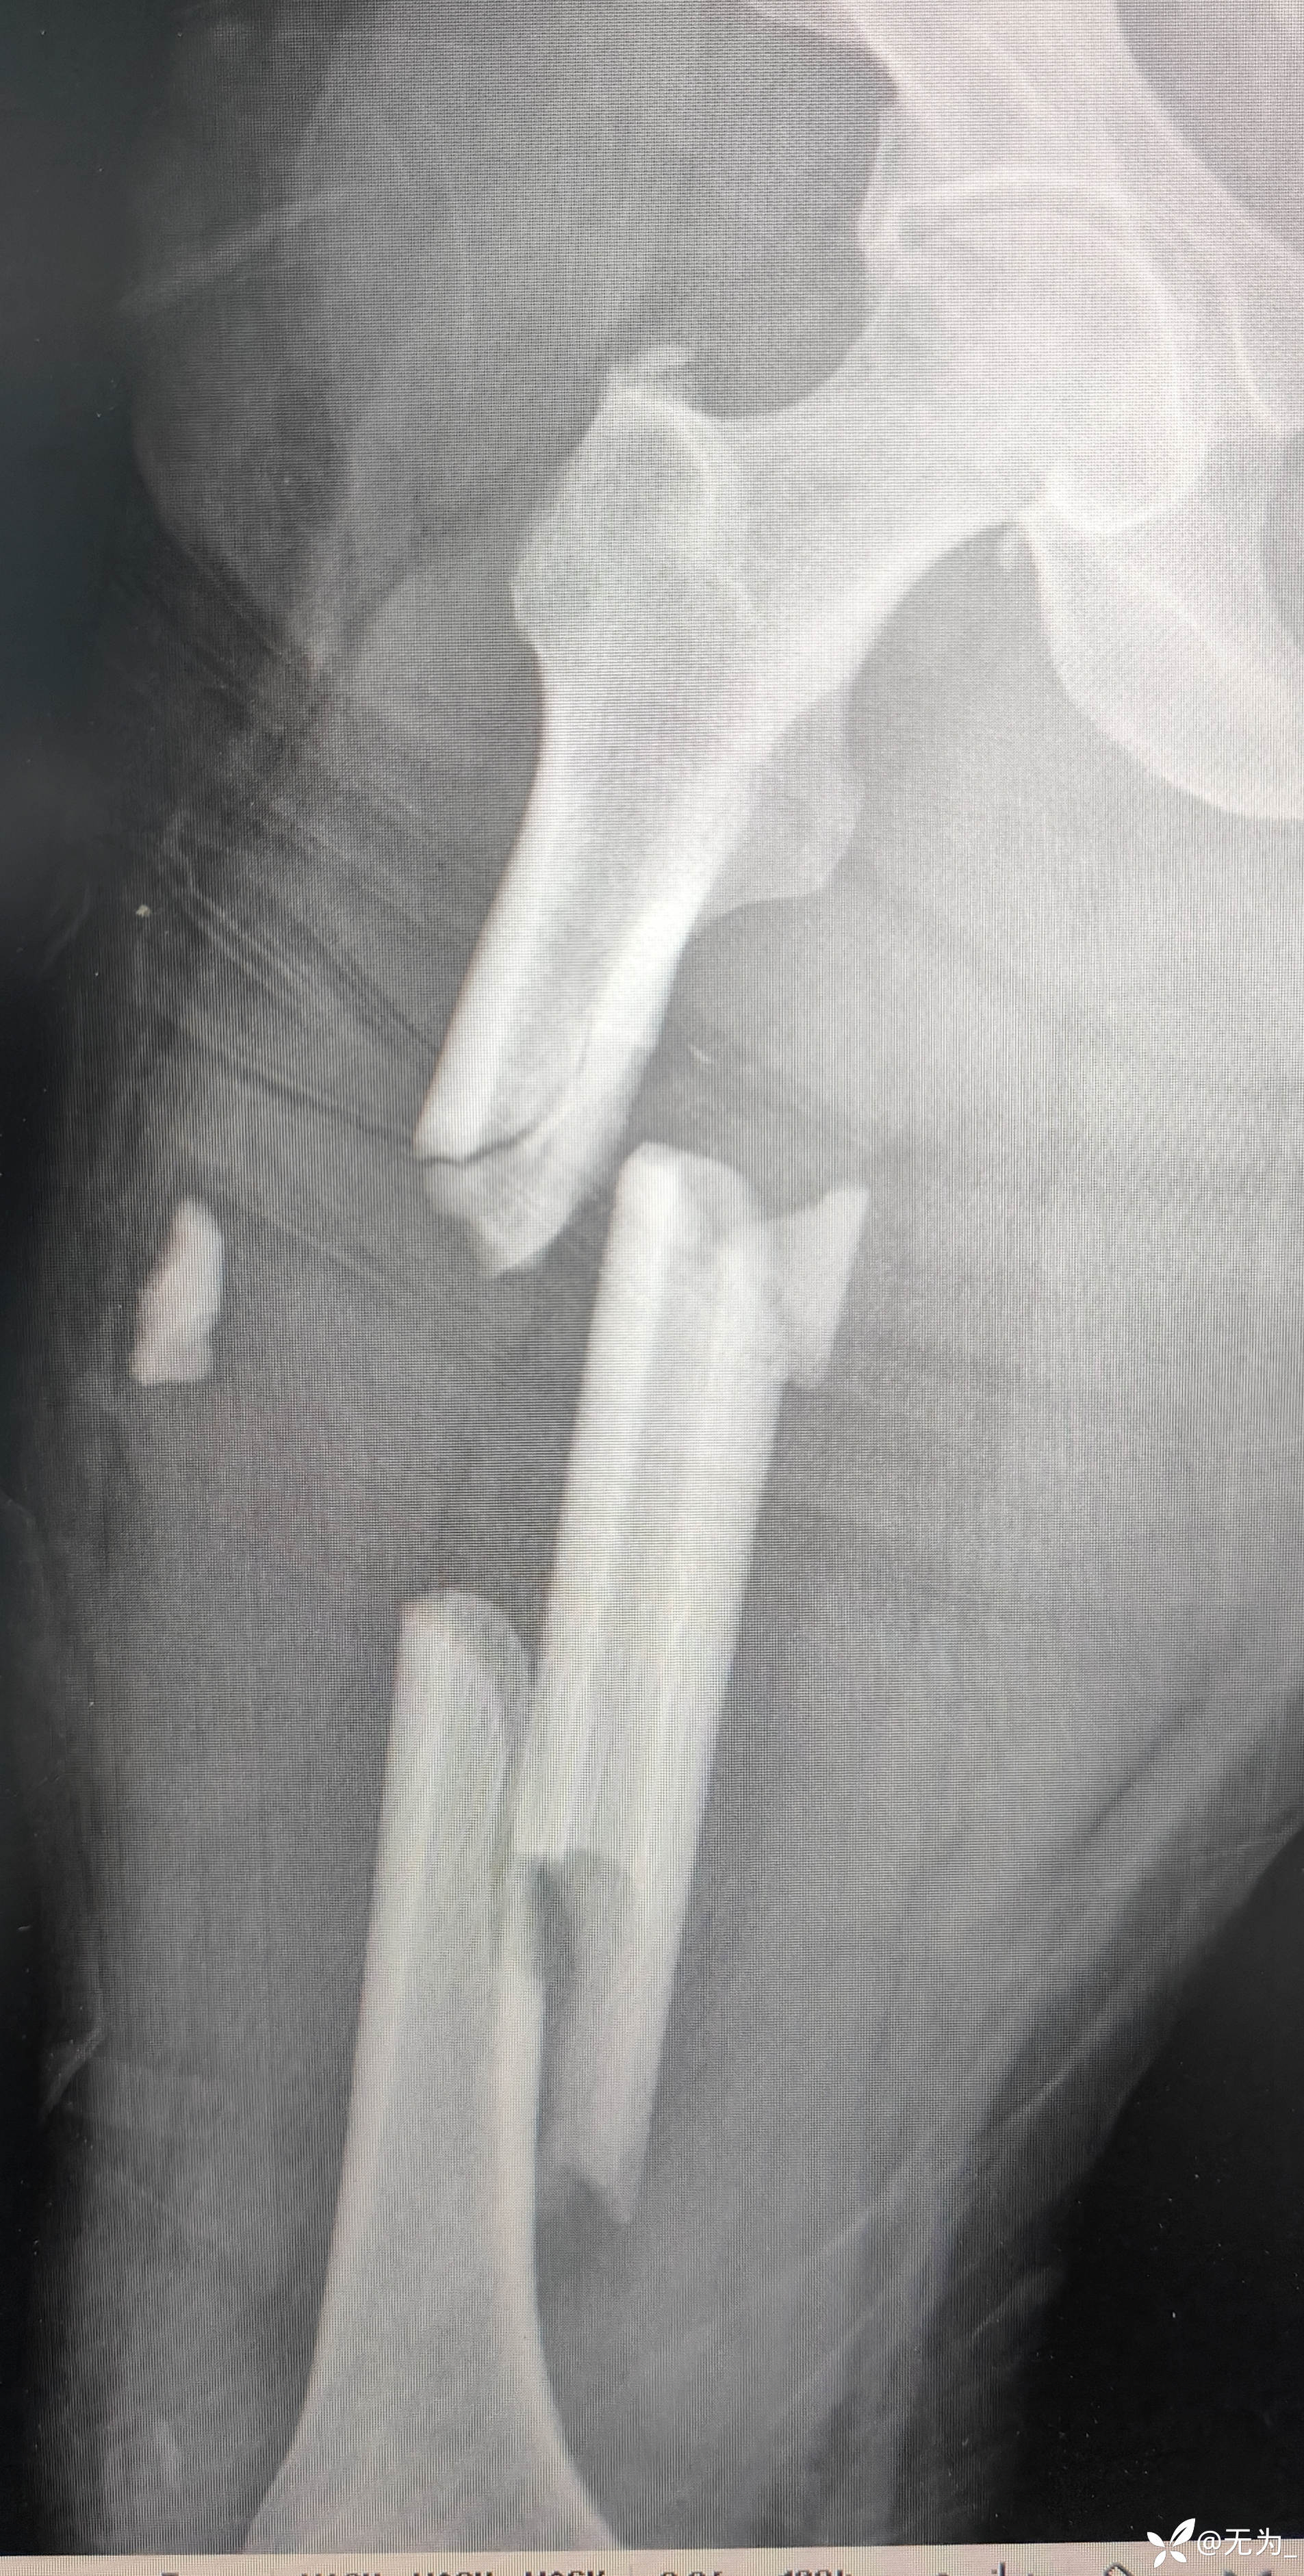

【患者信息】:患者55岁,车祸伤致全身多发骨折外院转入,生命体征不稳。

查体:右大腿中段前外侧两公分开放伤口,渗血,可处理游离骨块,大腿畸形、肿胀,足背动脉搏动可查。

补液、输血后行头外伤缝合、大腿外架临时固定,转icu,病情逐渐稳定,3周后行右股骨外架拆除,复位内固定。